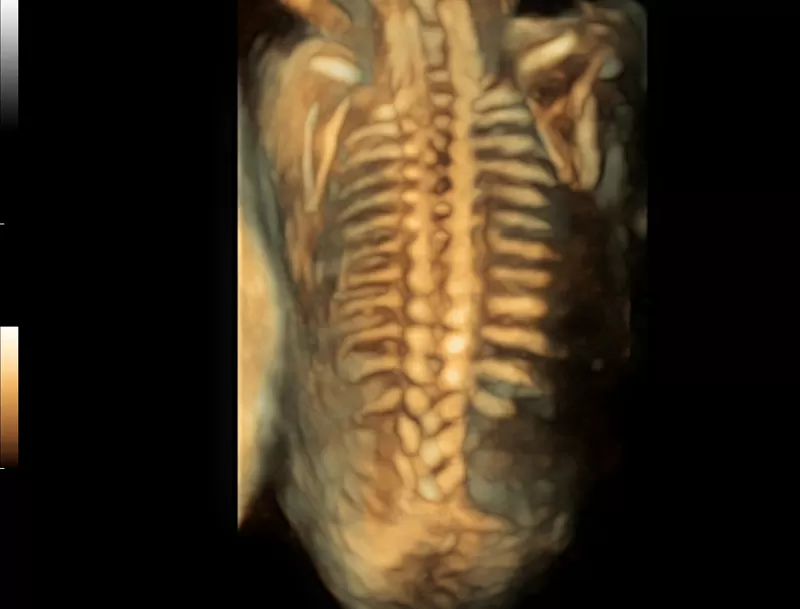

- New iLive with Hyaline